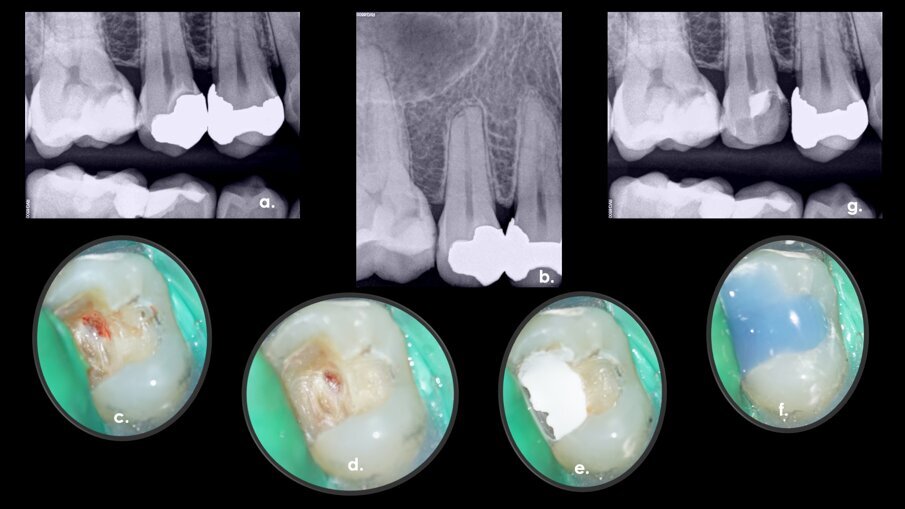

During an urgent appointment, a 35-year-old male patient reported sharp and short-lasting pain in tooth #15 in response to cold stimuli. The established diagnosis was reversible pulpitis and normal periapical tissue. During the removal of the old amalgam restoration, pulp exposure of approximately 3 mm in diameter was created at the level of the buccal pulp horn (Fig. 1a–g). As there was no profuse bleeding and the pulp diagnosis was reversible pulpitis, it was decided to proceed with a direct pulp capping procedure.

Fig. 1a–g: A direct pulp capping procedure sequence. Initial bitewing radiograph. The proximity of the previous restoration to the pulp space was evident (a). Initial periapical radiograph. No evidence of periapical disease (b). Pulp exposure (c). Pulp exposure after haemostasis, achieved after applying pressure with a sterile cotton pellet for 20 seconds (d). Placement of pulp capping material before removal of excess material in the peripheral areas (e). Non-radiopaque temporary restoration in place (f). Post-op radiograph taken at the end of the first appointment with the non-radiopaque temporary restoration in place (g).

After disinfection of the cavity using 2.5% sodium hypochlorite, a high-consistency calcium silicate-based material (CeraPutty, Meta Biomed) was used for direct pulp capping. At the end of the first appointment, a non-radiopaque temporary restoration (NexTemp LC, Meta Biomed) was placed with the objective of confirming by radiograph appropriate placement of the direct pulp capping material. A direct adhesive restoration was placed during the second appointment using composite (Ezfil, Meta Biomed).

The patient was asymptomatic after the treatment and responded normally to sensitivity tests during the follow-up sessions. A thick dentinal bridge was observed radiographically at the six-month follow-up appointment (Fig. 2). The restoration was well adapted at the three-year follow-up (Fig. 3).